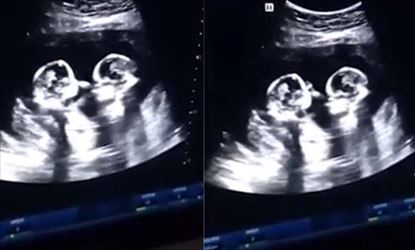

అయితే ఇది బాహ్య ప్రపంచంలో జరుగుతున్న దృశ్యం..మరి కడుపులోనే ఇద్దరు కవలలు కొట్టుకుంటే..ఈ వింత చూడటానికి కళ్లు సరిపోవడం లేదు. పుట్టకముందే పిల్లలు పొట్లాడుకోవడం ఎప్పుడైనా చూశారా? తల్లి కడుపులోనే ఇద్దరు కవలలు కొట్టేసుకున్నారు. కవలలు ఒకరిమీద ఒకరు పంచ్ విసురుకున్నారు. అదేంటీ కడుపులో పిల్లలు పంచ్ లు వేసుకోవడం ఏంటా అనుకుంటున్నారా..మీరే కాదు.. ఆల్ట్రా స్కానింగ్ తీసిన డాక్టర్లు కూడా అదే అనుకున్నారు. పంచ్ లు విసురుకుంటున్న కవలలను చూసి షాక్ అయ్యారు.

మహాభారతంలో అర్జునుడు ఒకసారి సుభద్రకు యుద్ధవిద్యలో పద్మవ్యూహం కష్టతరమైనది అంటూ పద్మవ్యూహంలో గురించి విరిస్తుంటే కడుపు లో అభిమన్యుడు వినడం గురించి మనకు తెలిసిన కథే. అయితే తల్లి కడుపులో హాయిగా నిద్రపోతున్న కవలలు.. ఎదురెదురుగా చేతులు ముడుచుకుని ఉండటాన్ని వైద్యులు చూసి ఆశ్చర్యపోయారు.

ప్రతి 30 మిలియన్ల కేసుల్లో ఇలాంటి అరుదైన ఘటనలు జరుగుతుంటాయని వైద్యులు తెలిపారు. అయితే ఈ కవలలు ఇద్దరూ ఆడపిల్లలు కావడం మరో విశేషం. ఈ స్కానింగ్ చేసిన నాలుగు నెలల తర్వాత చైనాలోని యుంచువాన్ ఆస్పత్రిలో ఈ కవలలు ఆరోగ్యంగా జన్మించారు. పుట్టిన ఇద్దరి బేబీలను పేరంట్స్.. చెర్రీ, స్ట్రాబెర్రీ నిక్ నేమ్ లతో ముద్గుగా పిలుకుంటున్నారు.